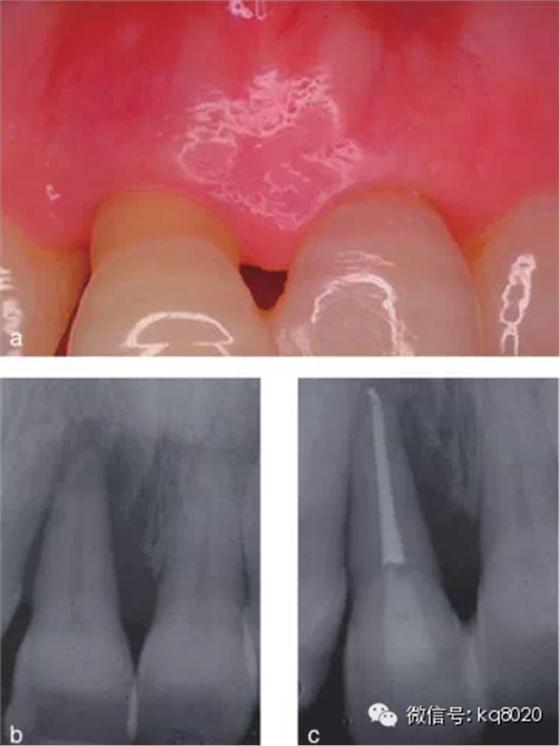

2011年,該研究團(tuán)隊的隨機(jī)對照臨床試驗,選擇已經(jīng)被診斷為臨床無望、伴有牙周牙髓聯(lián)合病變、牙周附著喪失達(dá)到或超過根尖的典型病例,分別選擇采用拔牙后固定替代修復(fù)(25例)和保存再生治療(25例),進(jìn)行對照,觀察遠(yuǎn)期療效(5年);對于牙髓無活力的聯(lián)合病變患者則先行根管治療,至少觀察3個月后再行牙周手術(shù);再生治療方式包括EMD、GTR、GTR+骨粉、EMD+骨粉、EMD+GTR共5種。結(jié)果顯示,對照組和試驗組均有顯著臨床改善,牙齒功能良好,5年觀察期內(nèi)80%以上患者隨訪無不適;試驗組僅有2顆牙齒療效不佳而予以拔除,平均臨床附著增加7.7±2.8mm,X線顯示骨量增加8.5±3.1mm,PD減少8.8±3mm,均控制在4±1.7mm內(nèi),牙齒松動度均明顯減輕。

結(jié)論證實,牙周治療可改善因骨下袋缺損和重度牙周附著喪失達(dá)根尖的無望牙的預(yù)后,且這種狀況會保持穩(wěn)定5年以上(圖1、2)。